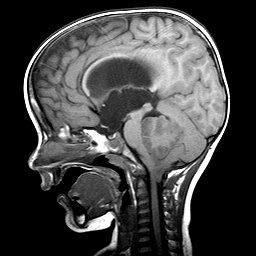

![]() Ependymoma of the 4th ventricle |

Ependymomas are predominantly tumors of children and adolescents. They arise most frequently in the fourth ventricle and cause hydrocephalus by blocking CSF flow. However, they may occur anywhere in relation to the ventricular system or central canal of the spinal cord and are the most common primary intra-axial tumors in the spinal cord and filum terminale. Ependymomas are well demarcated from the surrounding brain and grow in an exophytic fashion, protruding into and out of the fourth ventricle. Spinal ependymomas are circumscribed intra-axial masses. Some supratentorial ependymomas are exraventricular and may be cystic.